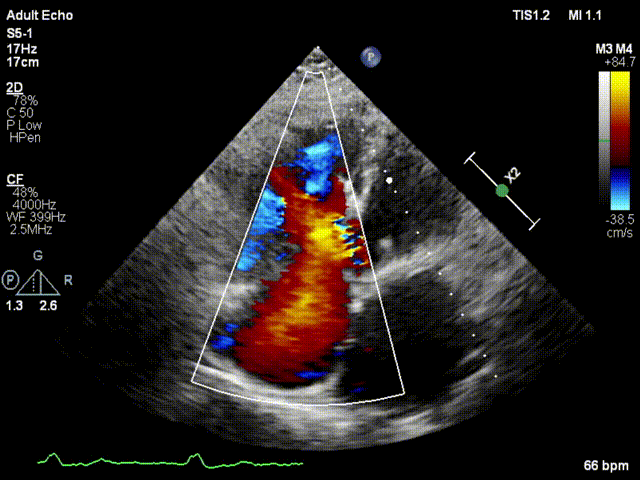

本次接受治療的患者是一名74歲的女性,14年前因風(fēng)濕性心臟病行二尖瓣生物瓣植入術(shù),合并房顫。近3年來反復(fù)因腹脹、納差、下肢水腫入院,藥物治療欠佳。心臟超聲顯示三尖瓣極重度反流(有效反流口面積:0.76cm²,反流容積:79ml),繼發(fā)性右房室增大及上、下腔靜脈增寬(右房上下徑*左右徑:52*41mm,右室左右徑:46mm,下腔靜脈:29mm),右室收縮功能正常,肺動(dòng)脈收縮壓 43mmHg,左心室射血分?jǐn)?shù)73% 。患者既往開胸手術(shù)史,術(shù)前評(píng)估STS 評(píng)分為7.02分,CRS 9分,無法接受體外循環(huán)下三尖瓣外科手術(shù)。面對(duì)這一傳統(tǒng)治療無法解決的困境,葛均波院士及其團(tuán)隊(duì)周達(dá)新教授、潘文志教授、張?jiān)床┦俊㈥惿┦考靶某业呐舜湔浣淌凇⒗顐ソ淌诮?jīng)過討論決定,采用創(chuàng)新的Lux-Valve Plus系統(tǒng)為患者進(jìn)行經(jīng)血管三尖瓣置換。

手術(shù)在患者全麻狀態(tài)下進(jìn)行,采用經(jīng)右側(cè)頸靜脈作為入路,將裝載有人工瓣膜的輸送器緩慢推送至右心房;并在經(jīng)食道超聲和DSA的引導(dǎo)下小心調(diào)整輸送器角度,將輸送器送入右心室;逐步釋放瓣膜錨定裝置和盤片,調(diào)整瓣膜位置后,錨定瓣膜完成植入。術(shù)后右房壓明顯下降,從術(shù)前的25/10(16) mmHg降至術(shù)后即刻的12/7(10) mmHg,術(shù)后超聲提示人工三尖瓣同軸性良好,固定牢固,無反流及瓣周漏,手術(shù)室即刻拔除氣管插管。